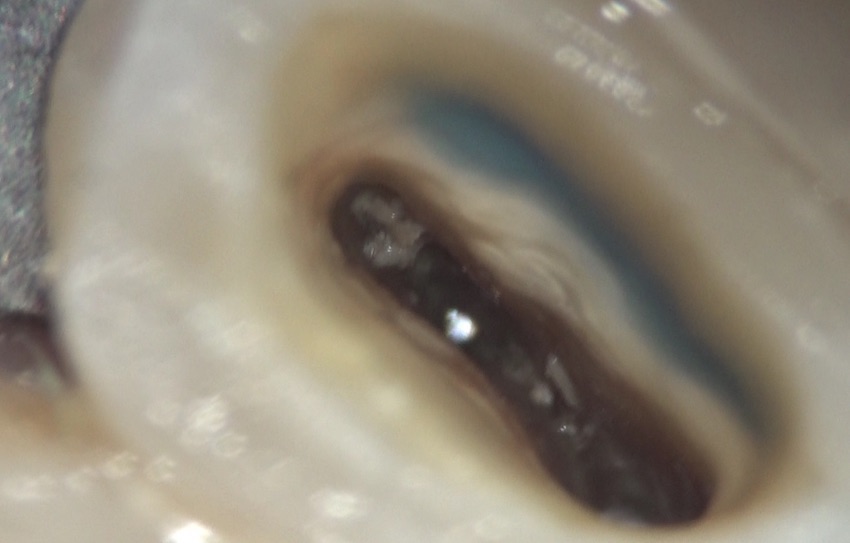

歯の内部をのぞいてみると・・・

このような状況。